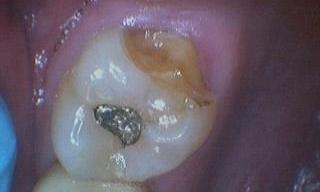

One of our patients from Auburn, NH broke a large part of their tooth. Since a cusp was missing, the tooth needed to be restored with a crown. We made a crown to fit over the existing tooth structure, and our patient’s tooth was restored!